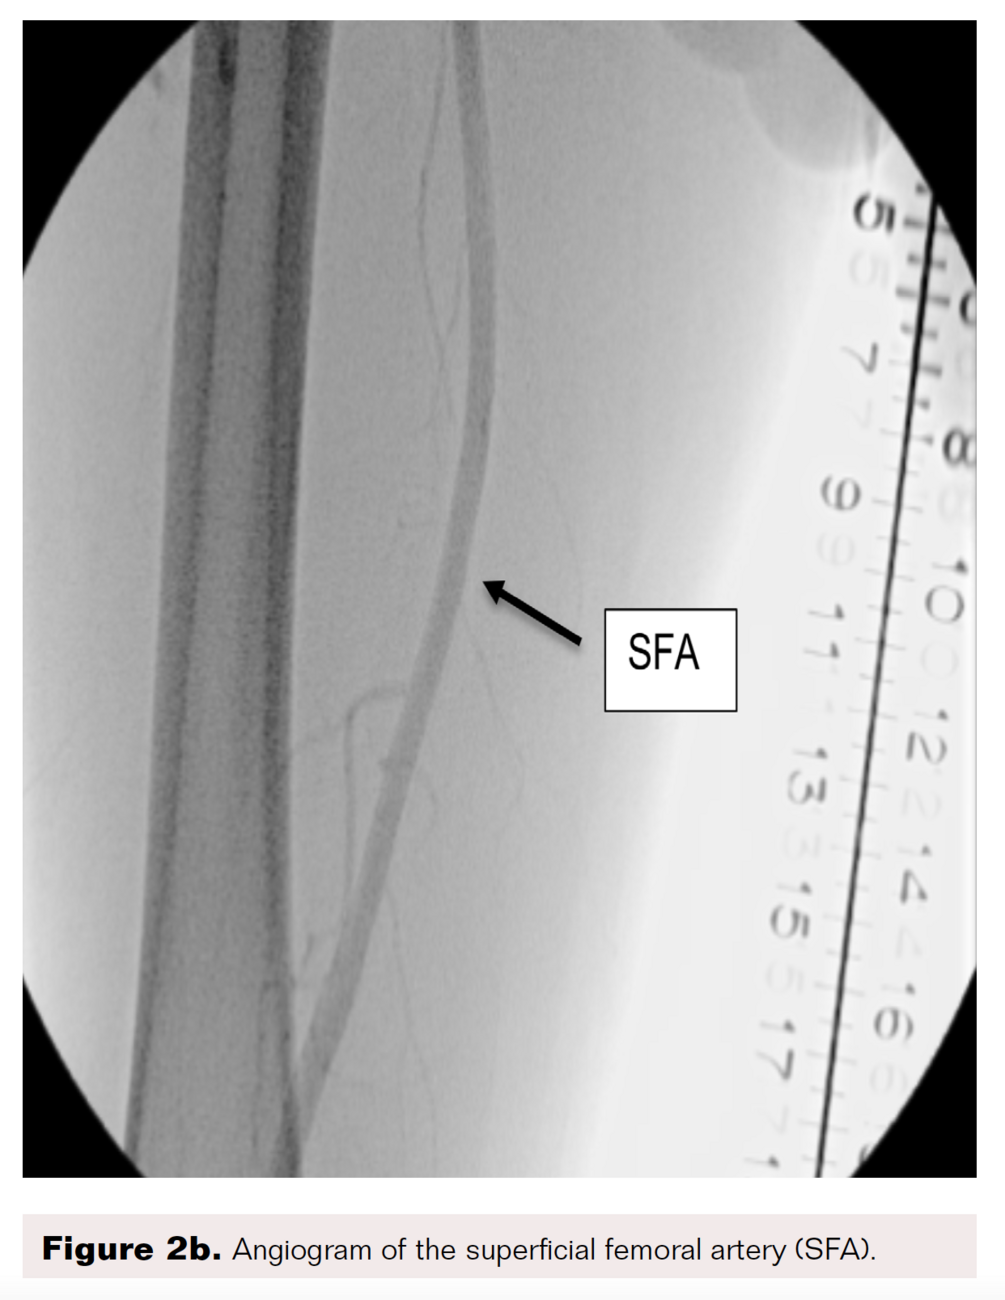

A right lower-extremity angiogram was performed using ultrasound guidance for antegrade access of the proximal superficial femoral artery (Figure 2A). Fluoroscopic acquisition demonstrated no significant disease in the superficial femoral artery (Figure 2B) and popliteal artery (Figure 2C), with no significant stenosis seen in the anterior tibial artery, PTA, and peroneal artery (Figure 2D). Pedal angiography demonstrated a complete pedal-plantar loop formed by the DPA and the lateral plantar artery (LPA) (Figure 2F).